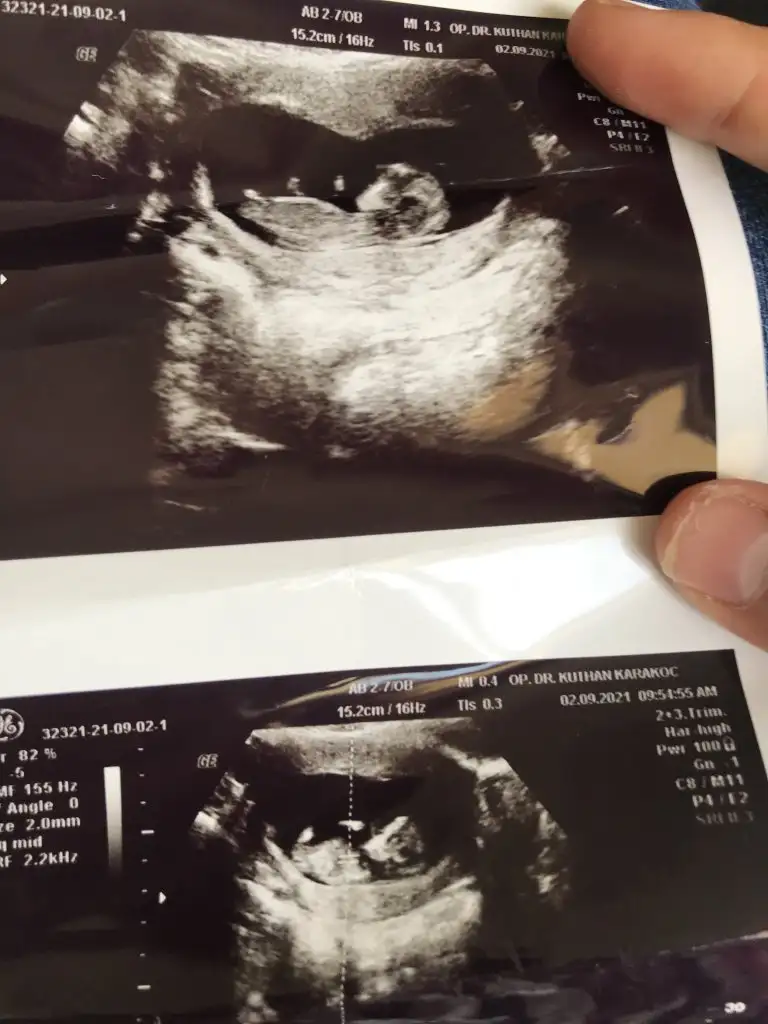

Emin olamadim kız gibi sankiBizde bugün kontrolden çıktık 12+3 haftalığız ,doktor cinsiyet için emin olamadı resimlerden siz yorum yapabilirmisinizIkra meyra

Erkek sanki sizin usgler net değilBu ultrason resmini gore bellimi acaba nub bi bakarmisiniz ikra meyra

Doktorda bir kız bi erkek dedi bakalım 3 hafta sonra kontrol var gösterir ozaman inşEmin olamadim kız gibi sanki

Net değil USG emin olamadımIkra meyra bu görüntümüz var ama sırtı dönük tahmin yapabilecek misin bu ultrasonda canım teşekkürler

Kız gibiKizlar bu da benim yavrum 12+3 sizce nedir çok merak ediyorumEki Görüntüle 2910088